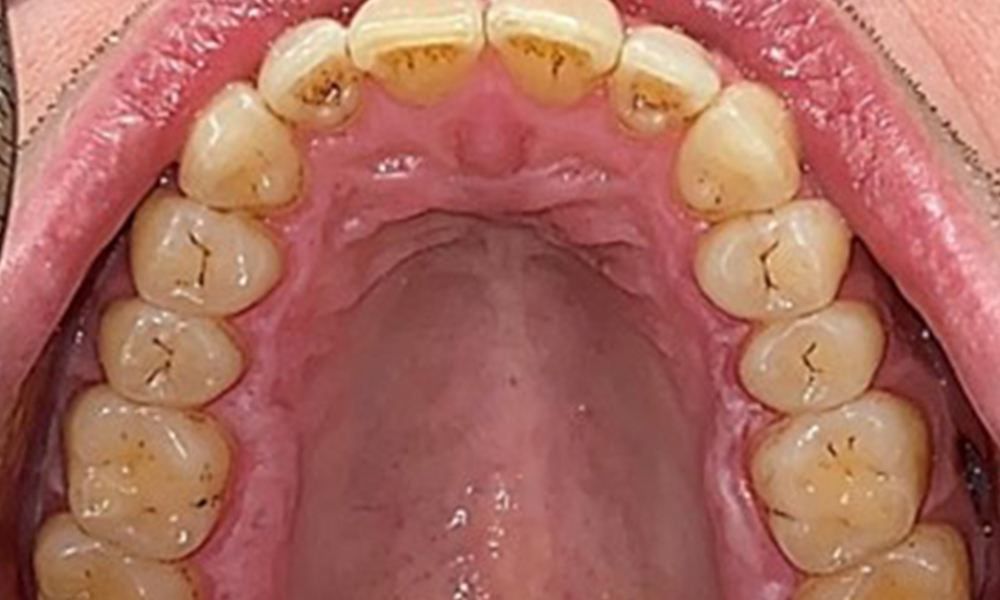

Dentaler Befund

Dental zeigt sich ein vollbezahntes Gebiss mit 28 Zähnen. Auffällig sind Erosionen und Attritionen

(Abb. 4, Abb. 5). Der Patient trägt seit vielen Jahren nachts eine Schiene mit adjustiertem Aufbiss aufgrund Bruxismus. Die Erosionen sind auf den langjährigen Konsum isotonischer Getränke zurückzuführen. Parodontaler Knochenverlust und aktive kariöse Läsionen sind nicht vorhanden.